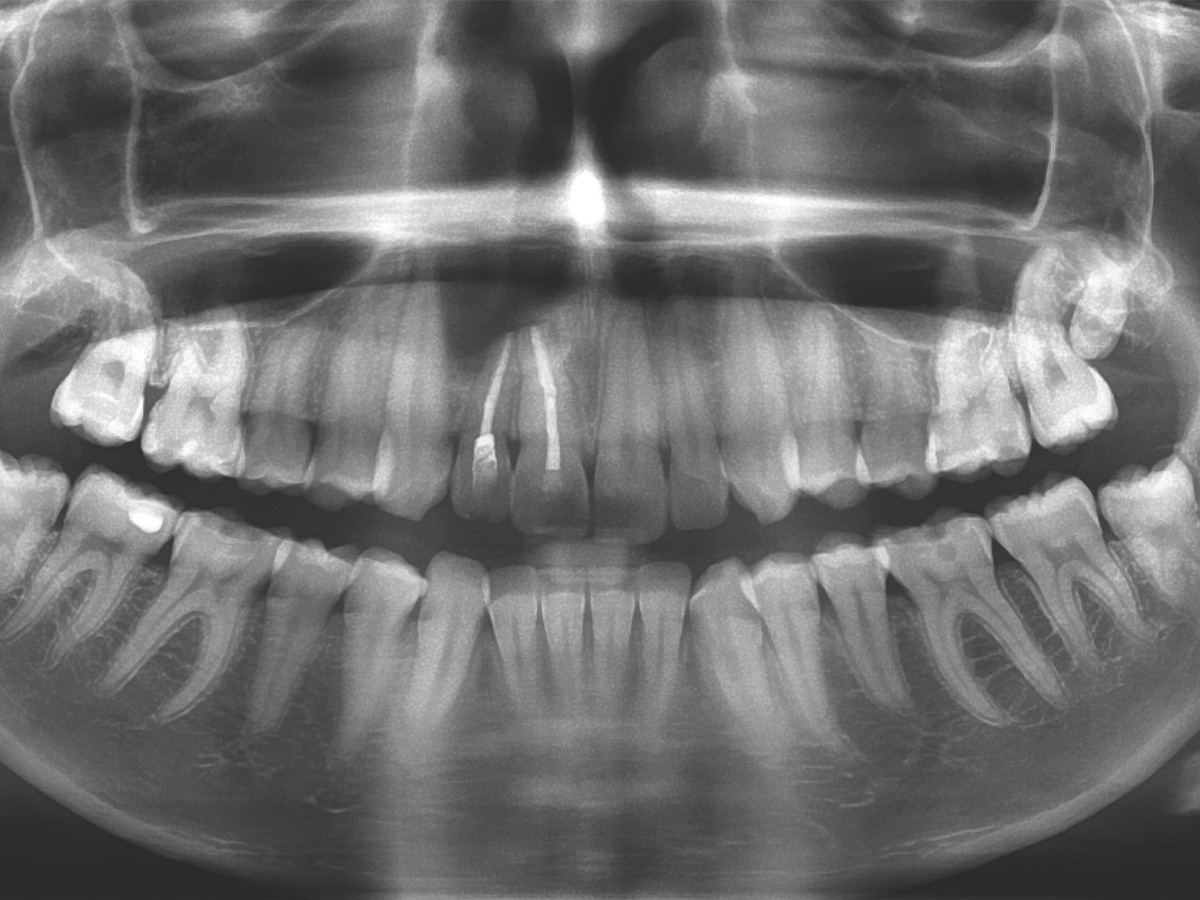

Abbildung 4

Prä-OP: Das OPG zeigt eine Erhellung im Knochenbereich regio 11 und 12.

Nach einem Zahntrauma im Jugendalter mit anschließender endodontischer Versorgung stellte sich unsere 24-jährige Patientin mit seit einigen Monaten bestehendem, rezidivierendem Druckgefühl und leichten Schmerzen in regio 11 und 12 vor (Abb. 1, 2, 3). Die klinische Untersuchung ergab an Zahn 11 und 12 Lockerungsgrad 1 und, wie zu erwarten, eine negative Sensitivität. Es lag ein leichter Perkussionsschmerz vertikal wie horizontal vor. Die Krone auf Position 11 zeigte eine leichte Verfärbung im Vergleich zu den Nachbarzähnen. Ein OPG ergab eine – in ihrer Ausdehnung nicht sicher zu beurteilende – Aufhellung im Knochenbereich regio 11 und 12 (Abb. 4). Als Nebenbefund waren teilretinierte Zähne 38 und 48 sowie ein vollständig retinierter Zahn 28 als Mikroform nachzuweisen. Ein zusätzlich durchgeführtes DVT zeigte eine große zystische Formation unter Einschluss der Wurzeln 11 und 12, die vom Canalis nasopalatinus bis mesial 13 mit einer kleineren Perforation zum Nasenboden und größeren Perforationen nach vestibulär und palatinal reichte (Abb. 5, 6, 7).